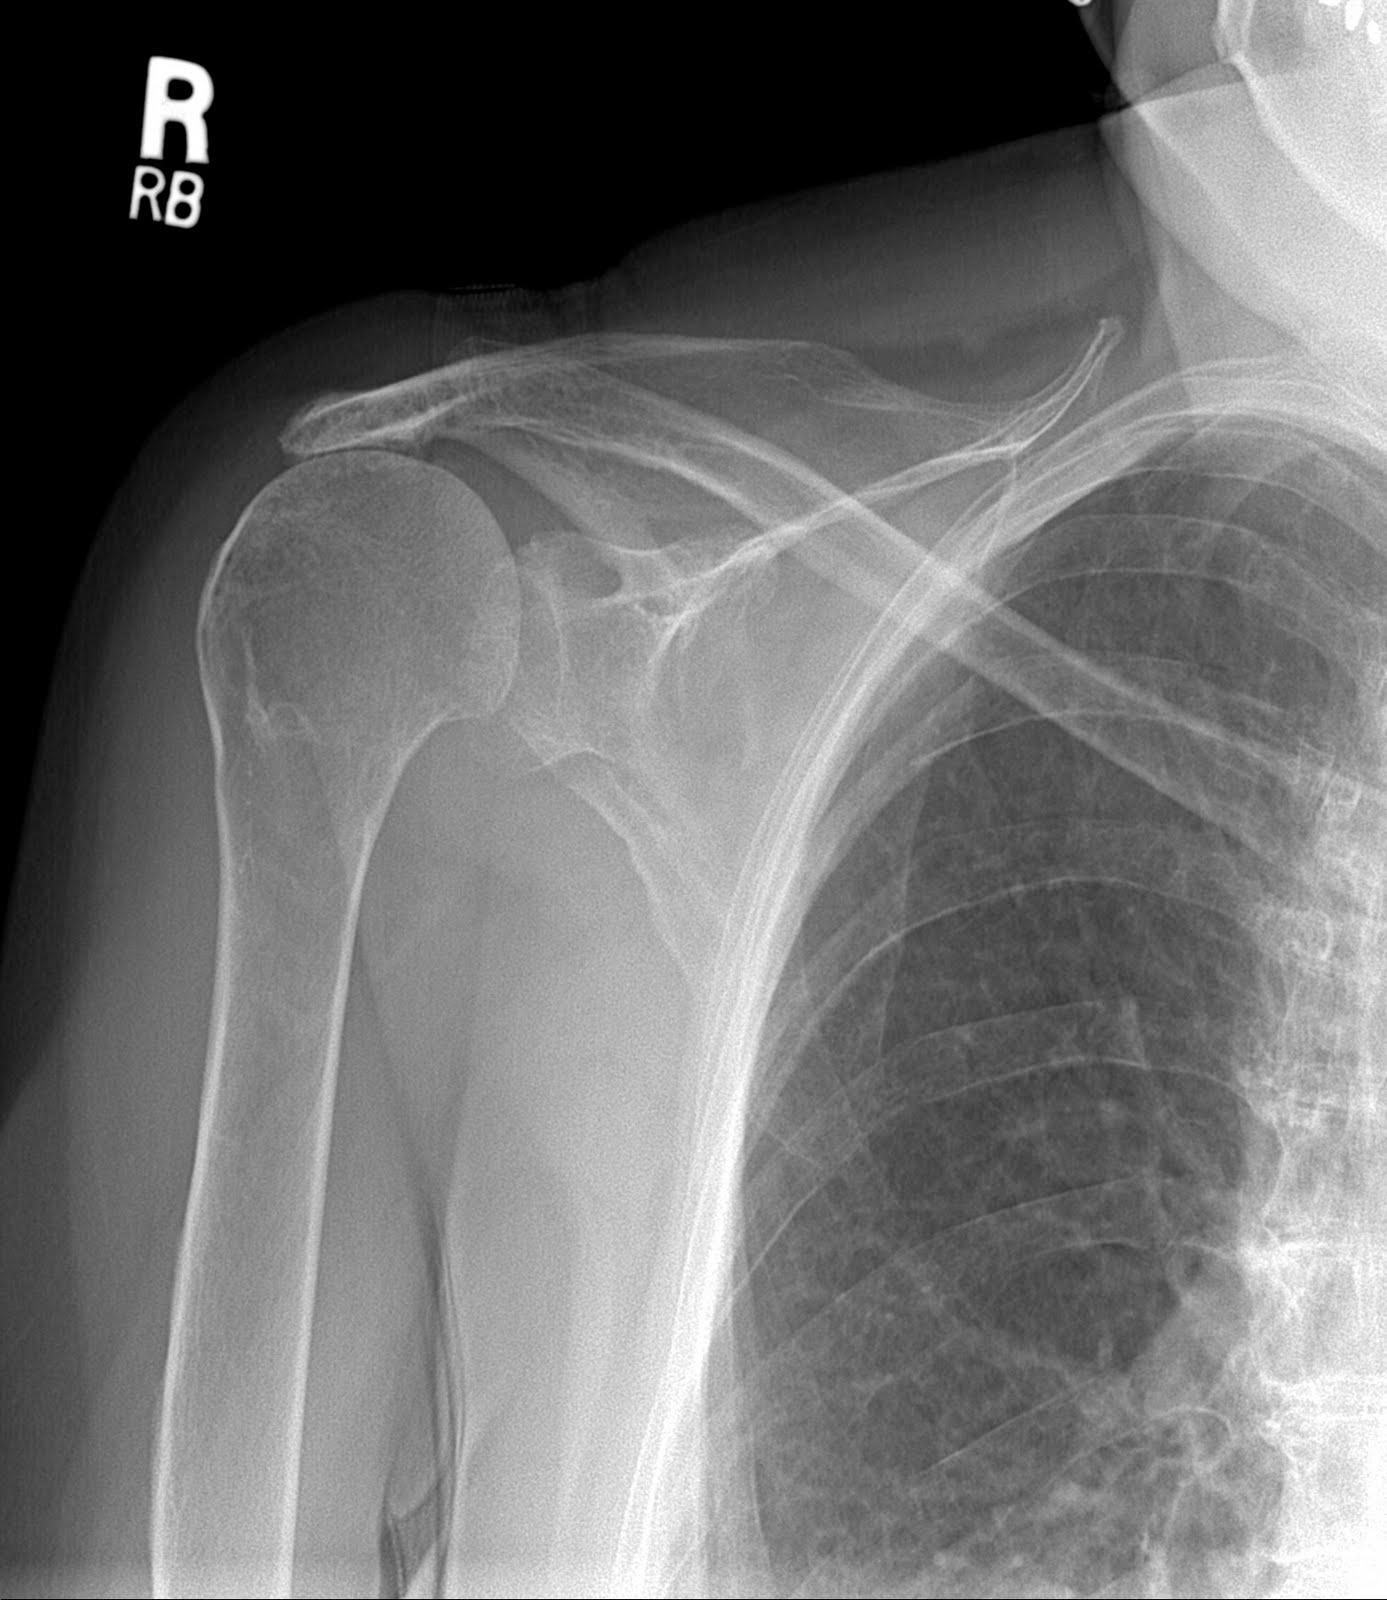

Below are the patient’s x-rays of the other shoulder taken at the same visit. What we see here is that the humeral head (the ball) is not in the center of the glenoid (the socket). It has moved upward out of the socket as a result of a massive chronic rotator cuff tear. If there were any cuff that could be fixed, it would not heal and would lead to a poor outcome.

This is another case that could benefit from a reverse should replacement if she had pain and an impairment that bothered her. The good thing is that this patient does not have any pain in her right shoulder. She has about 50% of a normal range of motion but has good function. I would leave well enough alone.